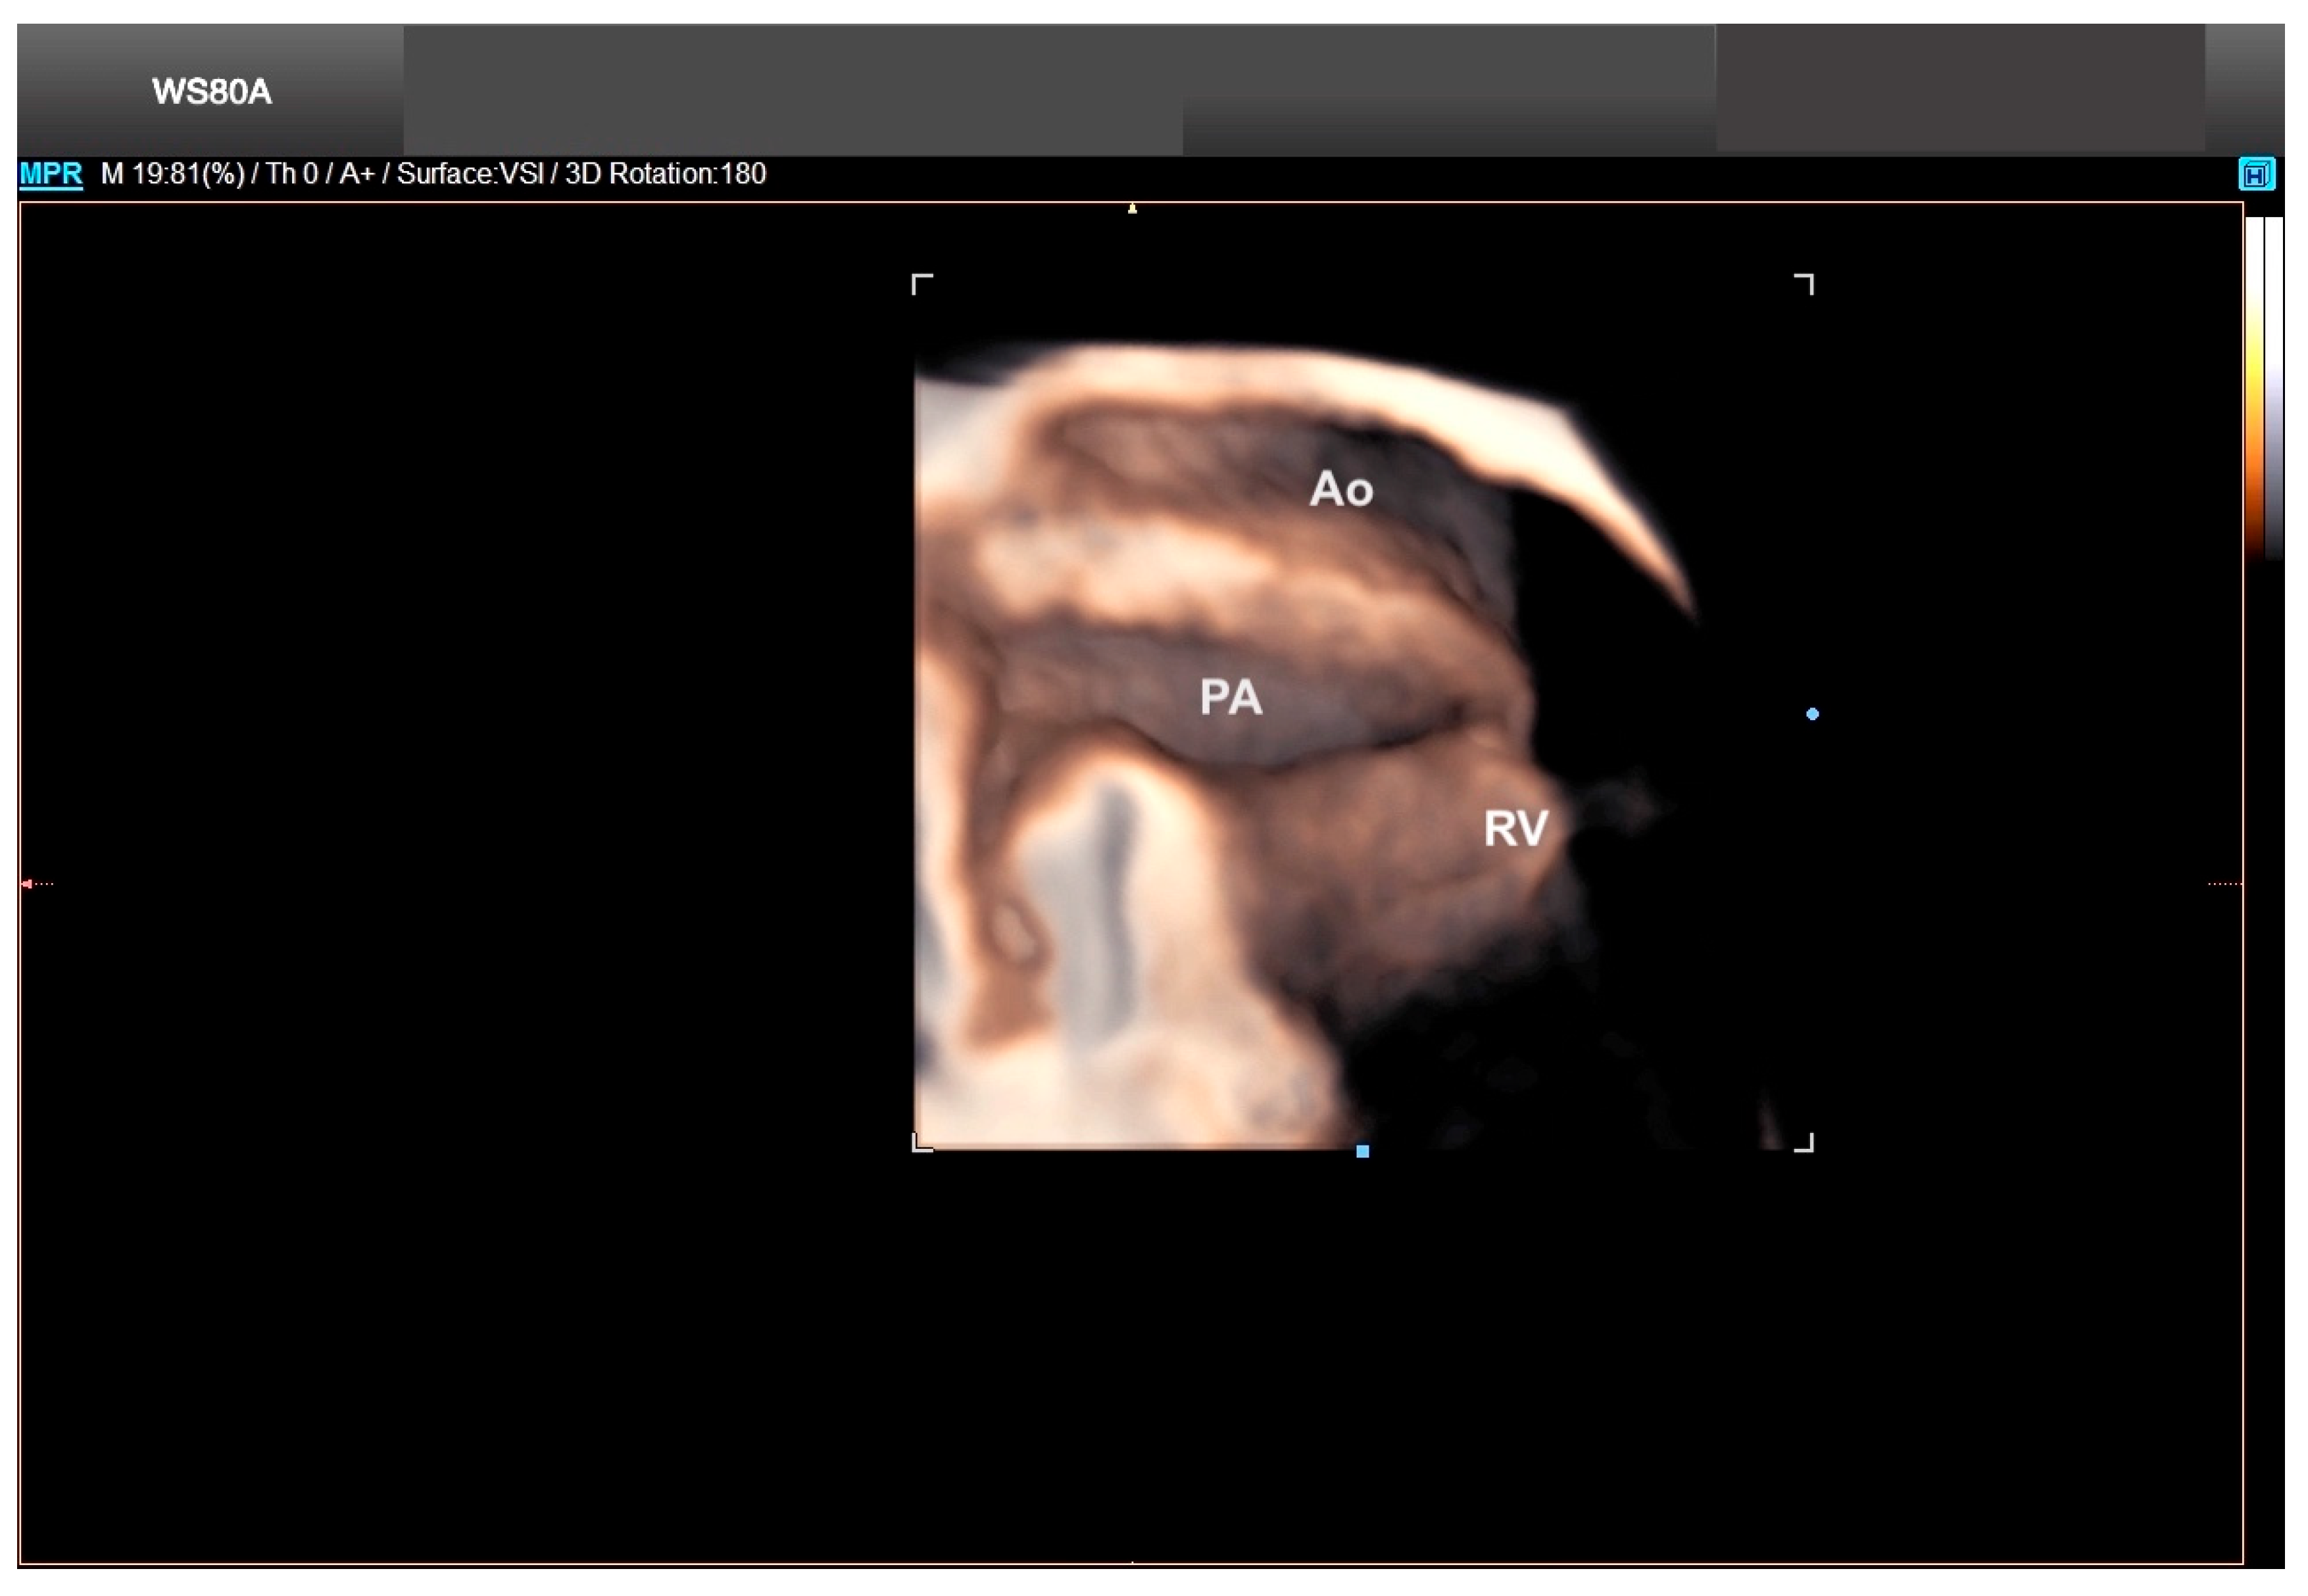

10. Transposition of the Great Arteries

- Rizzo, G.; Capponi, A.; Cavicchioni, O.; Vendola, M.; Pietrolucci, M.E.; Arduini, D. Application of automated sonography on 4-dimensional volumes of fetuses with transposition of the great arteries. J. Ultrasound Med. 2008, 27, 771–776. [Google Scholar] [CrossRef] [PubMed]